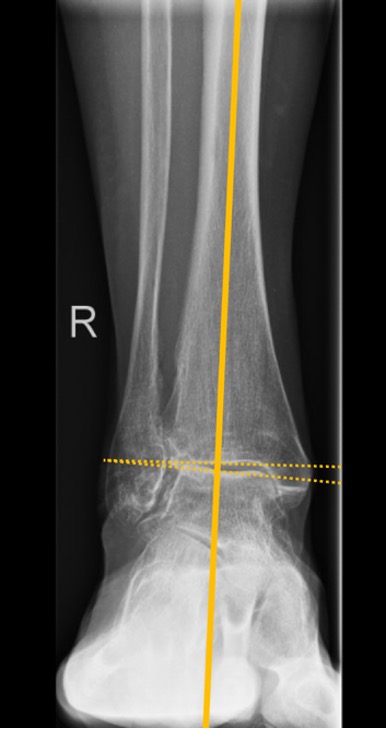

Figure 5. Measuring the deformity

- MDTA (TAS) is crucial for quantifying the supramalleolar deformity (Fig. 3)

- TTA normally defines the centre of rotation of angulation (CORA)

- Talar tilt should be used for quantitative assessment of an intra-articular deformity in the coronal plane. It is defined as the difference between the MDTA and the TTA

Talus tilt (TTA) = TTS – mDTAA

- Values of >4° are considered to be pathological